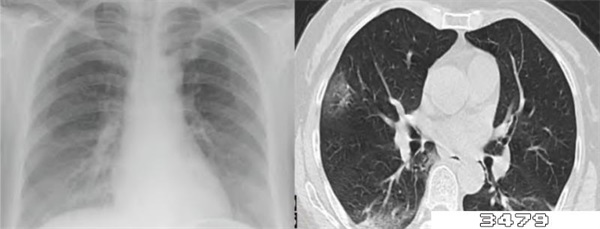

感染了新冠病毒的患者,如果是出现了低氧血症(血氧饱和度小于93%)、严重呼吸困难等症状的,一定要及时到医院的呼吸内科进行就诊,在就诊时可以辅以肺部x线检查、肺功能检查等。